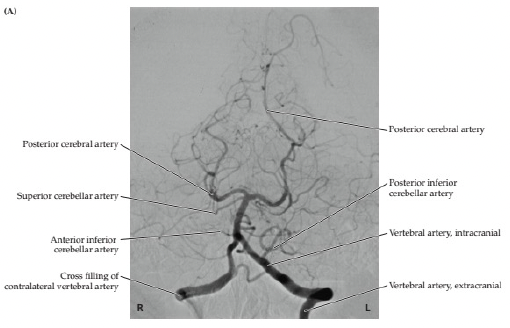

22

Q

ID the vessels

A